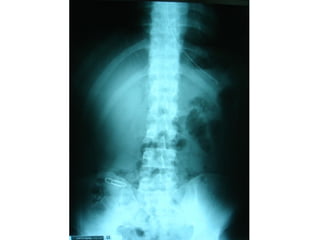

ชายไทยอายุ 28 ปี ถูกยิงที่ชายโครงด้านซ้าย 50

นาทีก่อนมารพ.

Primary survey

-airway and breathing:air hunger (o2 sat 88%)-----ET tube

check tube and lung----decrease breath sound Lt.lung

dullness on percussion--------hemoneumothorax Lt.lung

---ICD—blood 30 cc with minimal air leakage--02 sat 99%

Circulation and hemorrhage control

-BP แรกรับวัดไม่ได้ PR 110/min----iv load acetar 2500

cc

Hematcel 500 cc BP 125/72 mmHg PR 68/min ผู้ป่วยเริ่ม

ดิ้น

Neurological status:E1V1M1 pupil 5mm SRTL both

eye----E1VTM4 pupil 3mm SRTL both eye

Secondary survey

HEENT :on ET tube and NG tube

Heart:nomal s1 s2 no murmur ,no distance heart sound

,hypotension or jugular vein engorge

Lung:on Lt.ICD with hemopneumothorax Lt.chest

Gun shot wound at intercostal space 9-10 size 0.5cm

Abdomen:no distension,bowel sound absent

,soft ,dullness on percussion

PR: frank blood ,no sphincter tone

Back: gun shot wound(ทางออก) size 1 cm level

T11-T12

KUB:gross hematuria ,no bleeding per meatus

Intra operative finding